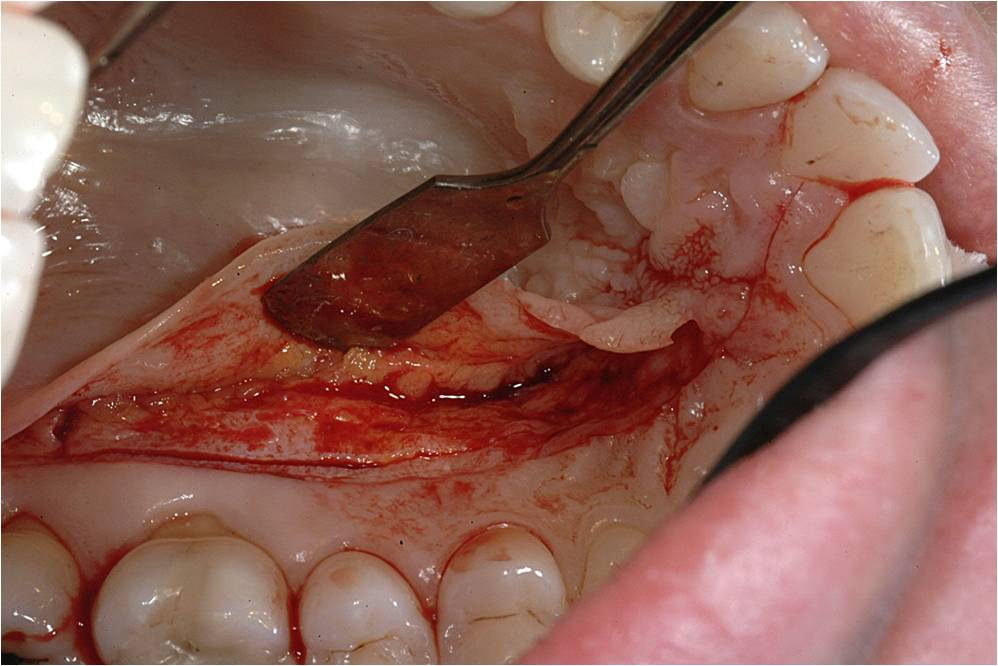

Harvesting a CTG requires displacing the epithelial layer to access the connective tissue.22 This can be accomplished with the creation of a “trap door” on the palate, which is made with a single horizontal incision. If more release is required, the incision is continued around the arch of the palate to the other side (Figure 7). The “trap door” consists of the outer epithelial layer and a thin layer of connective tissue; some connective tissue should remain on the flap to prevent sloughing during the healing process.15,21,22

Such an approach, which also leaves the periosteum of the palate intact, enables harvesting of ample connective tissue but also facilitates rapid donor site healing. The flap is lifted with a #15C scalpel (Figure 8), and the connective tissue is removed. Typically about 1.5 mm to 2 mm of tissue thickness and 4 mm to 6 mm of tissue width, by whatever length is necessary to cover the number of teeth involved, is harvested.22